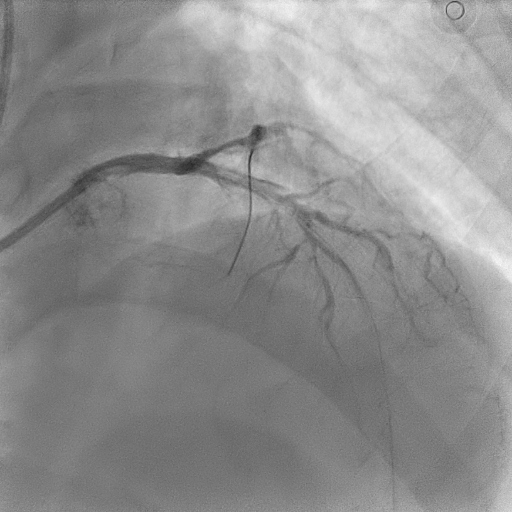

Coronary angiography revealed mild disease of the left main stem. The LAD exhibited severe proximal, mid, and distal disease of a diffuse nature. The LCx demonstrated severe mid–distal disease with a severely stenosed proximal obtuse marginal branch. The dominant RCA showed severe mid-vessel disease with significant involvement of the PL branch.

Mid–proximal LAD was sequentially prepared with SC 2.0 balloon and IVUS guidance; distal LAD underwent POBA with SC 1.5 balloon. Lesions in mid LAD and proximal LAD were refined with scoring balloons 2.5/15 and 3.5/15, respectively, treated with DCBs 2.5/30, 2.5/30 and3.5/25. A proximal Type C dissection sealed with a Fantom Encore BRS 3.0/24, post-dilated with NC 3.5/15. LCx and OM prepared with sequential SC balloons 1.5/15 and 2.0/15. Treated with DCBs 2.0/20 at proximal OM and 2.0/30 at LCx. RCA planned for staged angioplasty. Left coronaries were restudied at the time when patient was readmitted for staged angioplasty to RCA, showed excellent results. RCA prepared with POBA to the PL branch with 1.5 SC balloon, scoring balloon 2.5/15 to distal–mid RCA, followed by DCBs 2.75/40 and 3.0/30. A Type A dissection ensued in mid RCA, yet final TIMI III flow achieved.